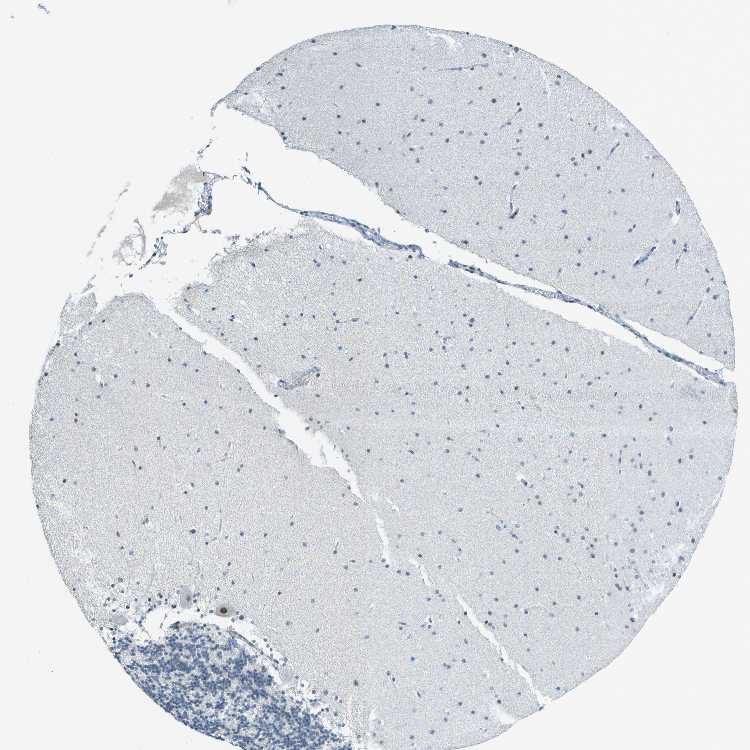

CEREBELLUM - Antibody stainingi

Antibody staining in the annotated cell types in the current human tissue is reported as not detected, low, medium, or high, based on conventional immunohistochemistry profiling in selected tissues. This score is based on the combination of the staining intensity and fraction of stained cells.

Each image is clickable and will lead to virtual microscopy that enables deeper exploration of all samples and also displays staining intensity scores, fraction scores and subcellular localization as well as patient and tissue information for each sample.

Antibody HPA016908

Purkinje cells High

Cells in granular layer Not detected

Cells in molecular layer Not detected